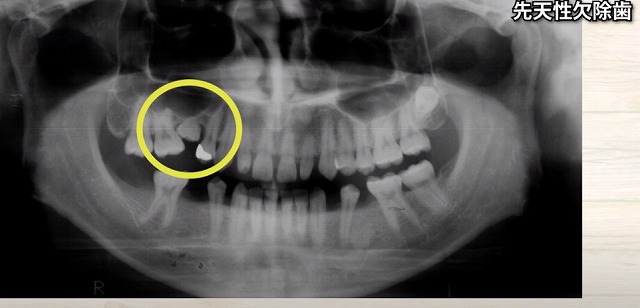

この方は

子供の歯の大人の歯に囲まれて

見えなくなっています。

何が

起こってしまったのでしょうか?

子供の歯より

後から大人の歯が生えてきていますから

その中で押し沈められてしまいます。

歯は簡単に沈んでしまいます。